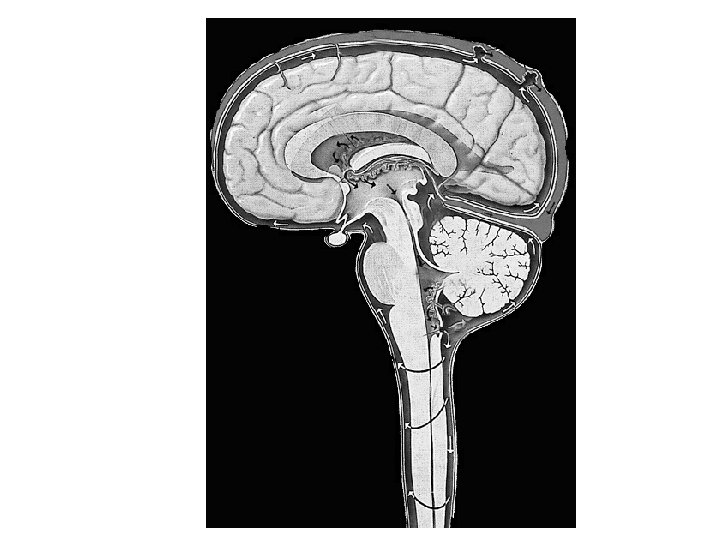

Posterior System Vertebral Ant. Spinal PICA Basilar AICA Sup Cerebellar Post Cerebral Post Communicating Anterior System Internal Carotid Middle Cerebral Anterior Cerebral Ant Communicating

Posterior System Medulla: Vertebral, Ant Spinal, PICA Pons: Basilar, AICA, Sup Cerebellar Cerebellum: PICA, AICA, Sup Cerebellar Midbrain: Sup Cerebellar Post Cerebral